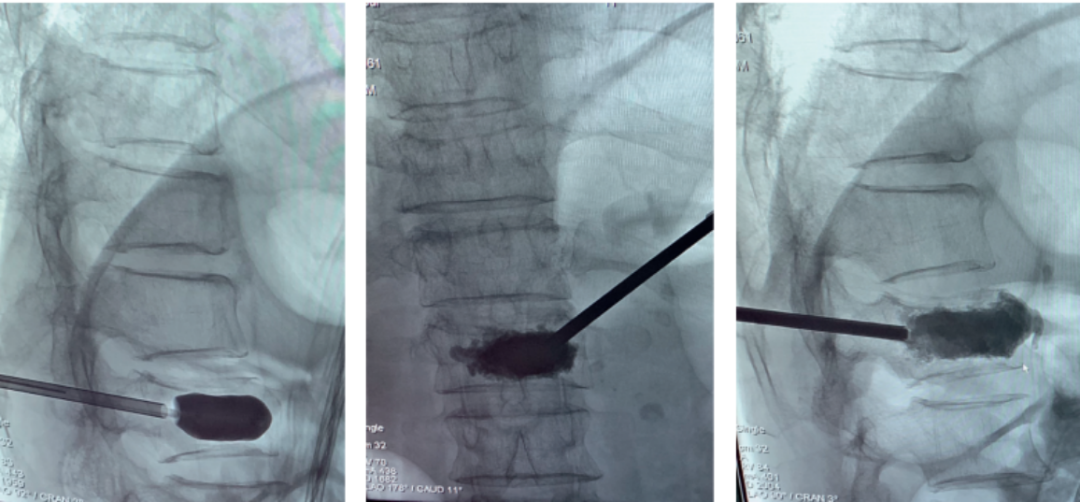

经皮球囊扩张椎体后凸成形术(PKP)

①正位、侧位影像监测下,经皮由椎弓根置入;

②置入导管球囊扩张,向气囊内充气扩张,以恢复椎体高度;

③放出气囊内气体,移走气囊,注入骨水泥维持矫正后形态

经皮球囊扩张椎体后凸成形术(PKP)病例